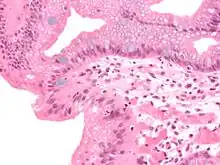

En anatomie pathologique, la métaplasie est la transformation d'un tissu cellulaire différencié en un autre tissu cellulaire différencié. Il s'agit d'un phénomène adaptatif et réversible qui se produit le plus souvent en réponse à une agression tissulaire répétée et prolongée (inflammation, irritation mécanique ou chimique, infection), le tissu de remplacement étant mieux armé que le tissu original contre ladite agression.

Dans la métaplasie, la structure et la fonction du nouveau tissu sont strictement normales, ce qui la distingue de la dysplasie (ou état précancéreux), bien qu'elle puisse évoluer secondairement vers ce stade si l'agression persiste.

La métaplasie ne peut être affirmée que par l'examen microscopique d'un prélèvement tissulaire. En pathologie humaine on la rencontre principalement dans quatre situations :

Dans le reflux gastro-œsophagien pathologique, la muqueuse du tiers inférieur de l'œsophage est exposée de façon chronique au pH acide du liquide gastrique, contre lequel elle n'est pas protégée. On peut assister à la transformation de l'épithélium malpighien normal en un épithélium glandulaire de type intestinal (métaplasie intestinale), donnant un endobrachyœsophage (ou œsophage de Barett), qui peut dans certains cas évoluer vers un adénocarcinome et nécessite donc une surveillance endoscopique.